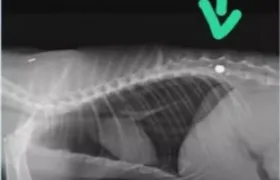

GERAL Gato é baleado no Rio e pode ficar sem movimentos São Gonçalo e Niterói estão entre as cidades que mais registram casos de maus-tratos aos animais